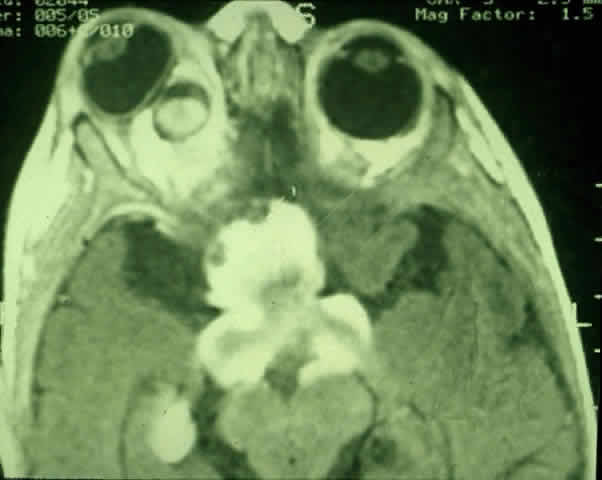

Proptosis is most common in patients with intraorbital tumors, although it can sometimes be observed in patients with concomitant chiasmal and intraorbital involvement3 (Figs. 1 and 2). Proptosis can be the presenting sign in glioma patients, and may even precede visual loss.13 Pain associated with the proptosis is not characteristic of optic gliomas.4 Minimal to severe proptosis, generally nonpulsatile and axial in nature, has been described, but it is typically in the range of 2 to 4 mm. Severe proptosis may jeopardize the health of the globe; it may also be a major cosmetic problem. The tumor itself is usually not palpable. Standardized A-scan examination of optic nerve gliomas demonstrates echograms of regular, homogeneous, low-to-medium reflectivity. On B-scan examination, large optic nerve gliomas appear as fusiform masses replacing the optic nerve void.41 In contrast to optic gliomas, meningiomas are typically irregular in structure and demonstrate higher internal reflectivities.41,42 The 30° test is usually negative when performed on gliomas because of the solid infiltration of the nerve; however, positive tests have been noted, suggesting perioptic subarachnoid fluid surrounding the tumor.42

Fig. 1. Five-month-old infant presenting with progressive proptosis caused by an optic pathway glioma. There is mechanical restriction of the motility of the affected right eye.

Fig. 2. Contrast-enhanced T1-weighted axial MRI of the orbits of the patient in Figure 1, demonstrating a large optic pathway glioma with posterior extension into the optic tracts and radiations. (Courtesy of Orlando Ortiz, MD, and Jeffrey Hogg, MD)